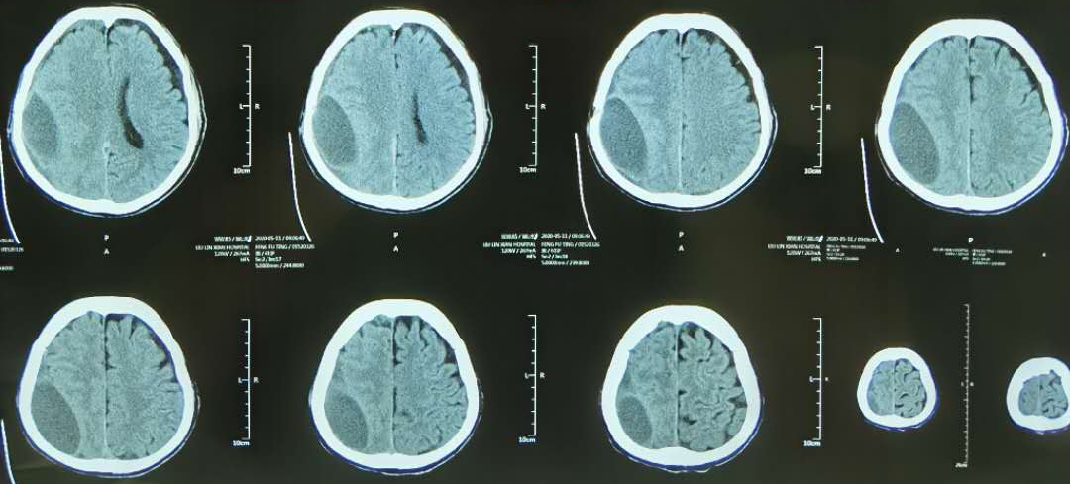

患者的艱難經(jīng)歷幫助醫(yī)生成長(zhǎng)——1例頑固性慢硬血腫在藥物治療下終于緩解